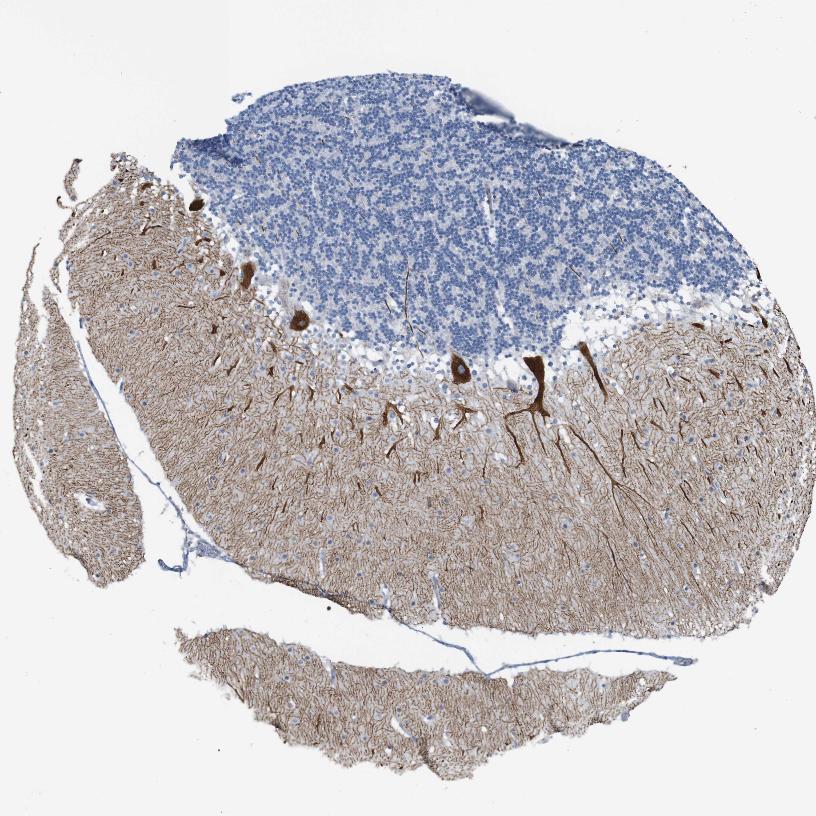

BRAIN CEREBELLUM Show tissue menu

CEREBELLUM - Expression summary

CEREBELLUM - Antibody stainingi

Antibody staining in the annotated cell types in the current human tissue is reported as not detected, low, medium, or high, based on conventional immunohistochemistry profiling in selected tissues. This score is based on the combination of the staining intensity and fraction of stained cells.

Each image is clickable and will lead to virtual microscopy that enables deeper exploration of all samples and also displays staining intensity scores, fraction scores and subcellular localization as well as patient and tissue information for each sample.

Antibody HPA014765Antibody HPA016487

Purkinje cells High-

Purkinje cells - cytoplasm/membrane -High

Purkinje cells - dendrites -High

Purkinje cells - nucleus -Not detected

Processes in granular layer -High

Processes in white matter -High